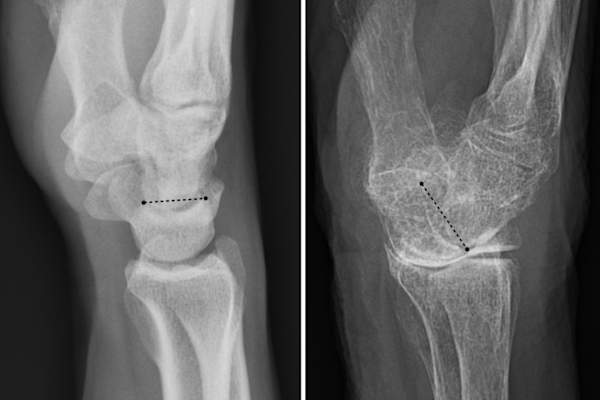

一个正常的手腕(左图)和一个(右图)由于骨质疏松导致腕关节倾斜。

一个正常的手腕(左图)和一个(右图)由于骨质疏松导致腕关节倾斜。 Nevit Dilmen和的MikaelHäggström

患有类风湿关节炎的妇女患骨质疏松症的风险更高